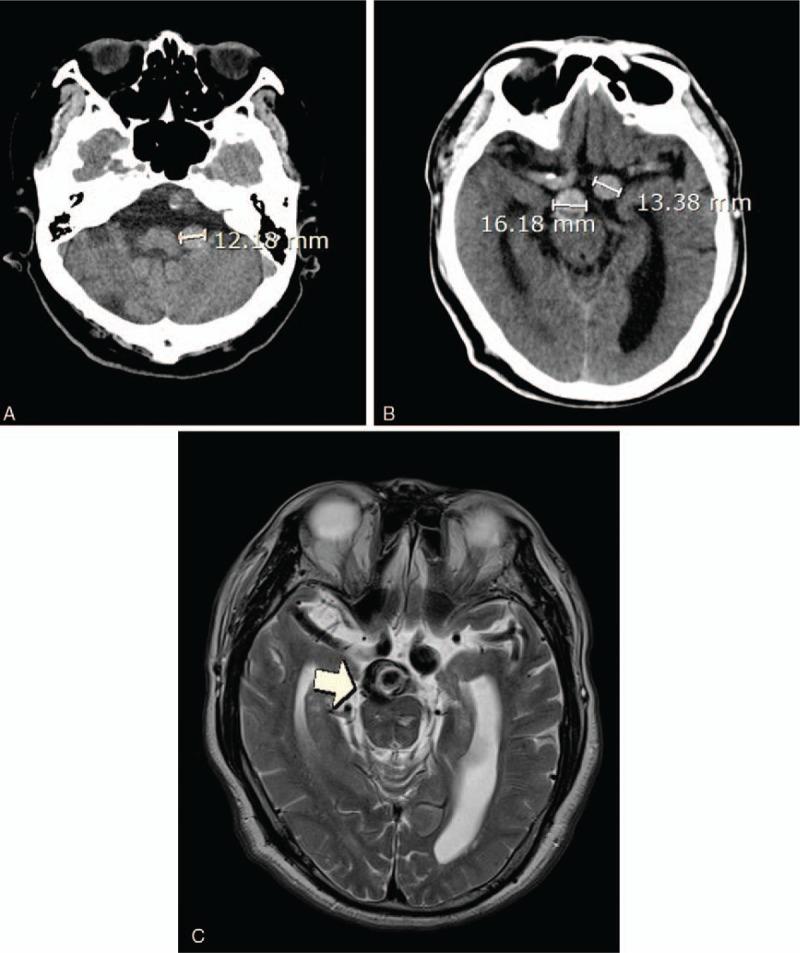

A 52-year-old male was admitted with headache and visual field defect.

Computed tomography and magnetic resonance imaging showed noncommunicating hydrocephalus due to vertebrobasilar dolichoectasia.

一名52岁男性因头痛和视野缺损入院。

计算机断层扫描和磁共振成像显示因椎基底动脉延长扩张导致的非交通性脑积水。